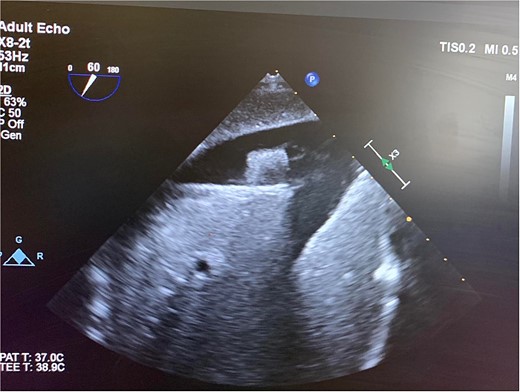

In the OR, exploratory laparotomy, right nephrectomy, liver packing, and pericardial window were performed. The pericardial window was negative for blood. With no suspected cardiac injury, intraoperative fluoroscopy (Fig. 1) and transesophageal echocardiogram (TEE) (Fig. 2) were used to locate the bullet. It was suspected to be intravascular secondary to venous embolism from the retro-hepatic inferior vena cava (IVC). Cardiothoracic surgery was consulted for removal of the bullet. With abdominal hemorrhage controlled, the surgeons agreed the patient was an acceptable risk for anticoagulation and cardiopulmonary bypass. Sternotomy was performed, the patient was placed on cardiopulmonary bypass, and the bullet was removed through a right atriotomy.

Intraoperative TEE demonstrating the intravascular bullet in the IVC.

Case 1 involved a stable patient with a single GSW to the left back and a retained bullet over the right ventricle. The trauma team identified the bullet overlying the cardiac silhouette and performed a CT scan to determine its trajectory. The scatter artifact complicated localization, but a pericardial window excluded cardiac injury. Intraoperative imaging (fluoroscopy and TEE) revealed a venous bullet embolism from the retro-hepatic IVC to the right ventricle. The bullet was mobile on fluoroscopy, and TEE provided the best imaging. The trauma and cardiothoracic surgeons discussed bullet removal timing, considering the patient’s stability and heparinization needs. They opted for immediate removal due to the potential lethality of pulmonary artery embolism. The operation was successful, requiring only one surgery for definitive management. This case highlights the success of immediate bullet removal in hemodynamically stable, asymptomatic patients with venous embolism.